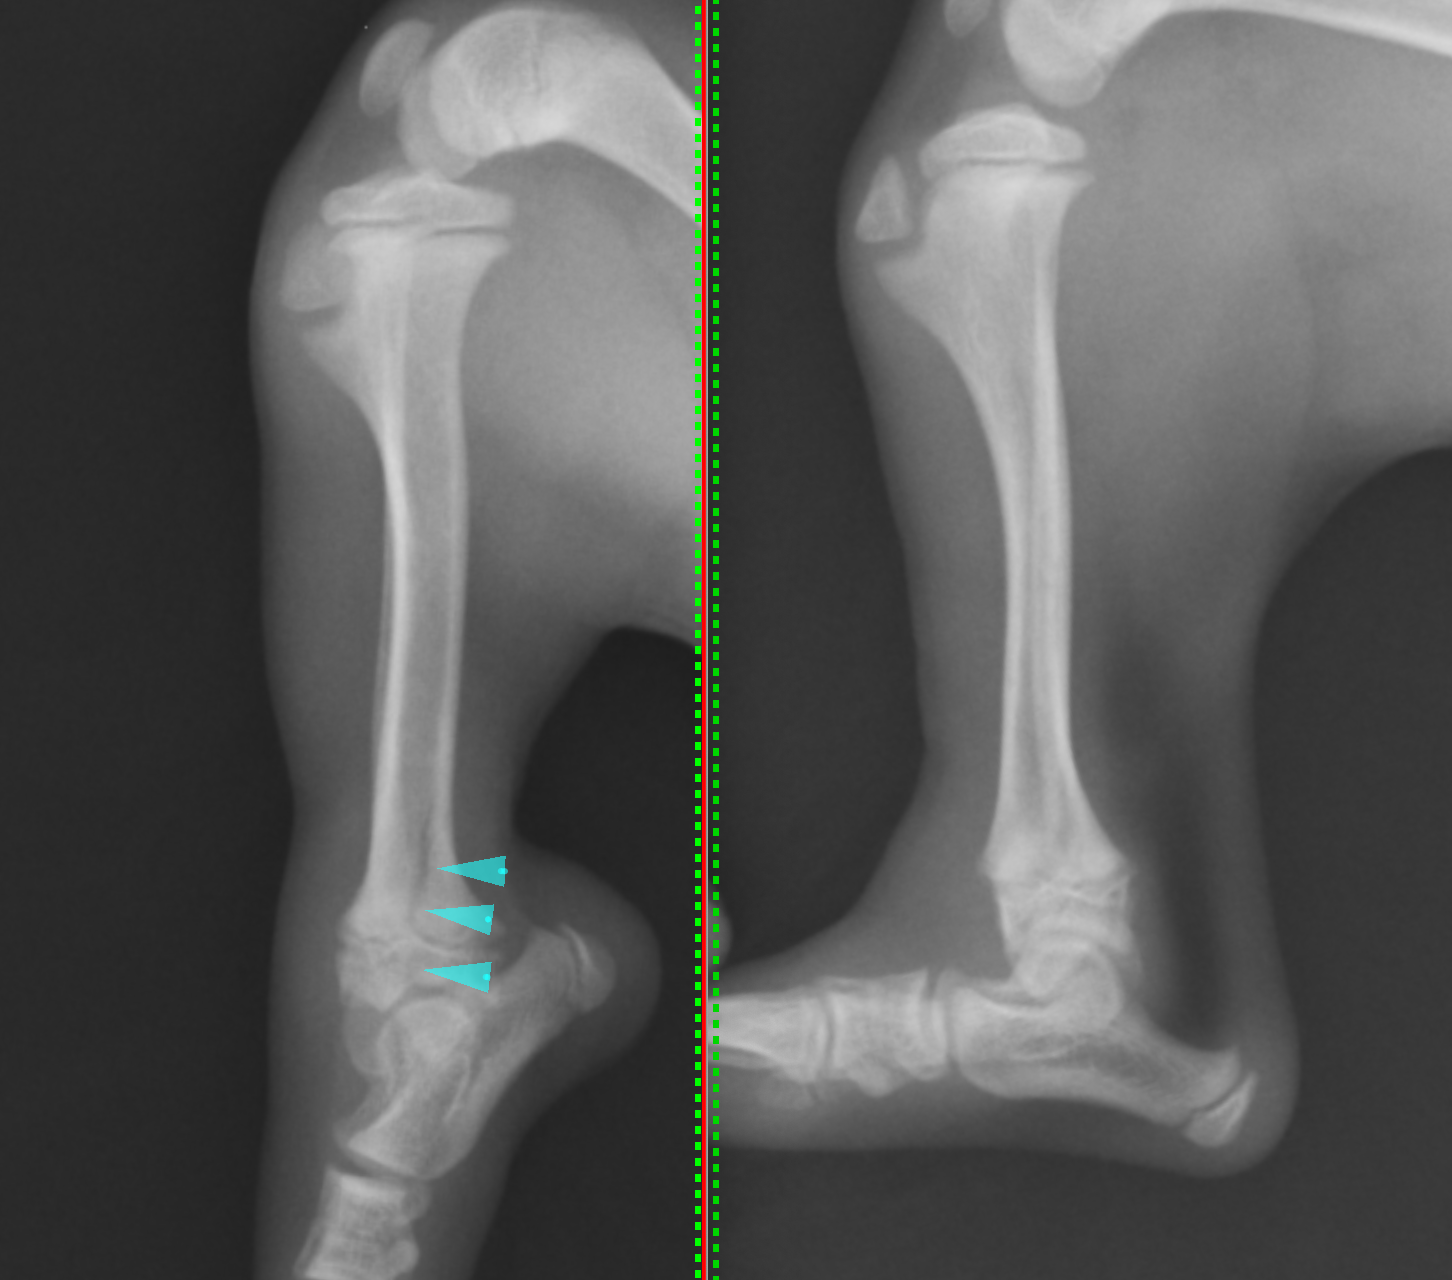

最初のレントゲンでは異常箇所がはっきりと分かりませんでしたが、ストレス撮影(伸ばしたり、曲げたりした状態で撮影すること)を行ったところ骨折箇所がわかりました。

通常の撮影法で撮影したレントゲン画像です。緑矢印の黒く抜けているところが成長板と呼ばれる部分になります。

左がストレス撮影したレントゲン画像です。青矢印の部分に亀裂が入っているのが確認されました。成長板をまたいで骨折しており、サルターハリス型骨折のタイプⅣであると診断しました。この子は不幸中の幸いで、完全に骨折したわけではなく、若木骨折という状態で一部はまだくっついている状態でした。

関節を曲げ伸ばしした際に常に痛みがでている、放っておくと成長がうまくできなくなる、若木骨折が完全骨折になるなどを考慮し、すぐに手術することとなりました。サルターハリス骨折の場合には関節面をピッタリと合わせることが重要となります。